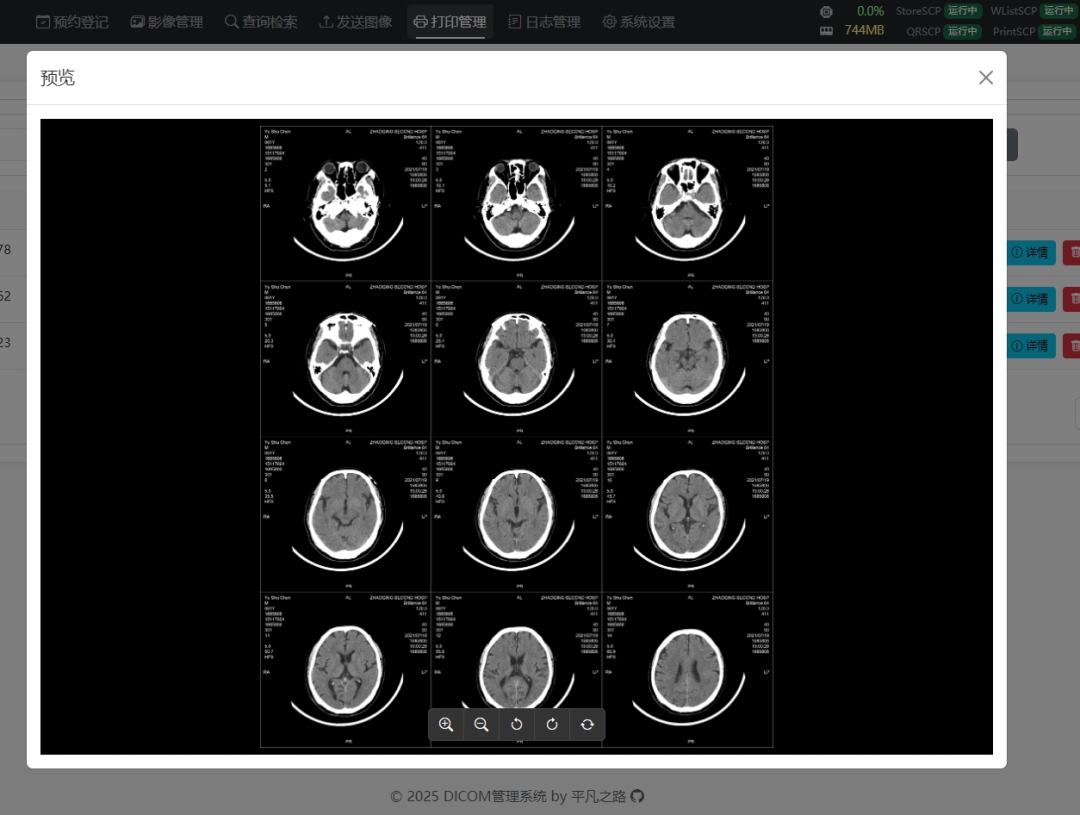

功能演示

图片